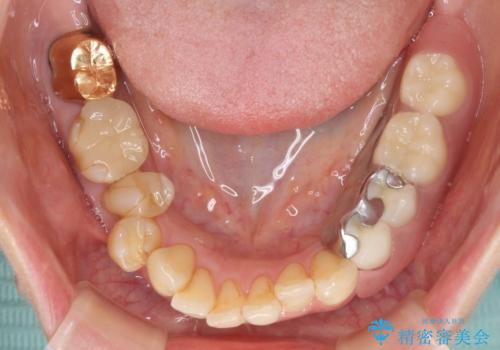

ノンクラスプデンチャー(金属止め具のない入れ歯)で左側の咬合回復

- 奥歯が痛いことを主訴にご来院された患者様です。入院してしまい、治療を2年間放置してしまったとのことでした。

左上は、抜歯とブリッジ治療を行いました(抜歯前に医師と対診)。

左下は、現在も抗がん治療を続けているため、観血的処置(インプラントなどの外科)はなるべく避けたいとのことで入れ歯を希望されました。それに伴い、入れ歯を支える歯のクラウンやりかえも行いました。

患者様はインプラント等の外科処置は希望されなかったため、セラミックと義歯で治療を行いました。

義歯を製作する際は、支えとなる歯の治療も同時に行うことで、義歯の製作が容易になります。

今回もそのように製作したところ、適合がよく安定のよい義歯になりました。患者様本人も使っていて全く痛くないとのことで、追加の調整もなく使用して頂いてます。患者様には、大変満足して頂きました。